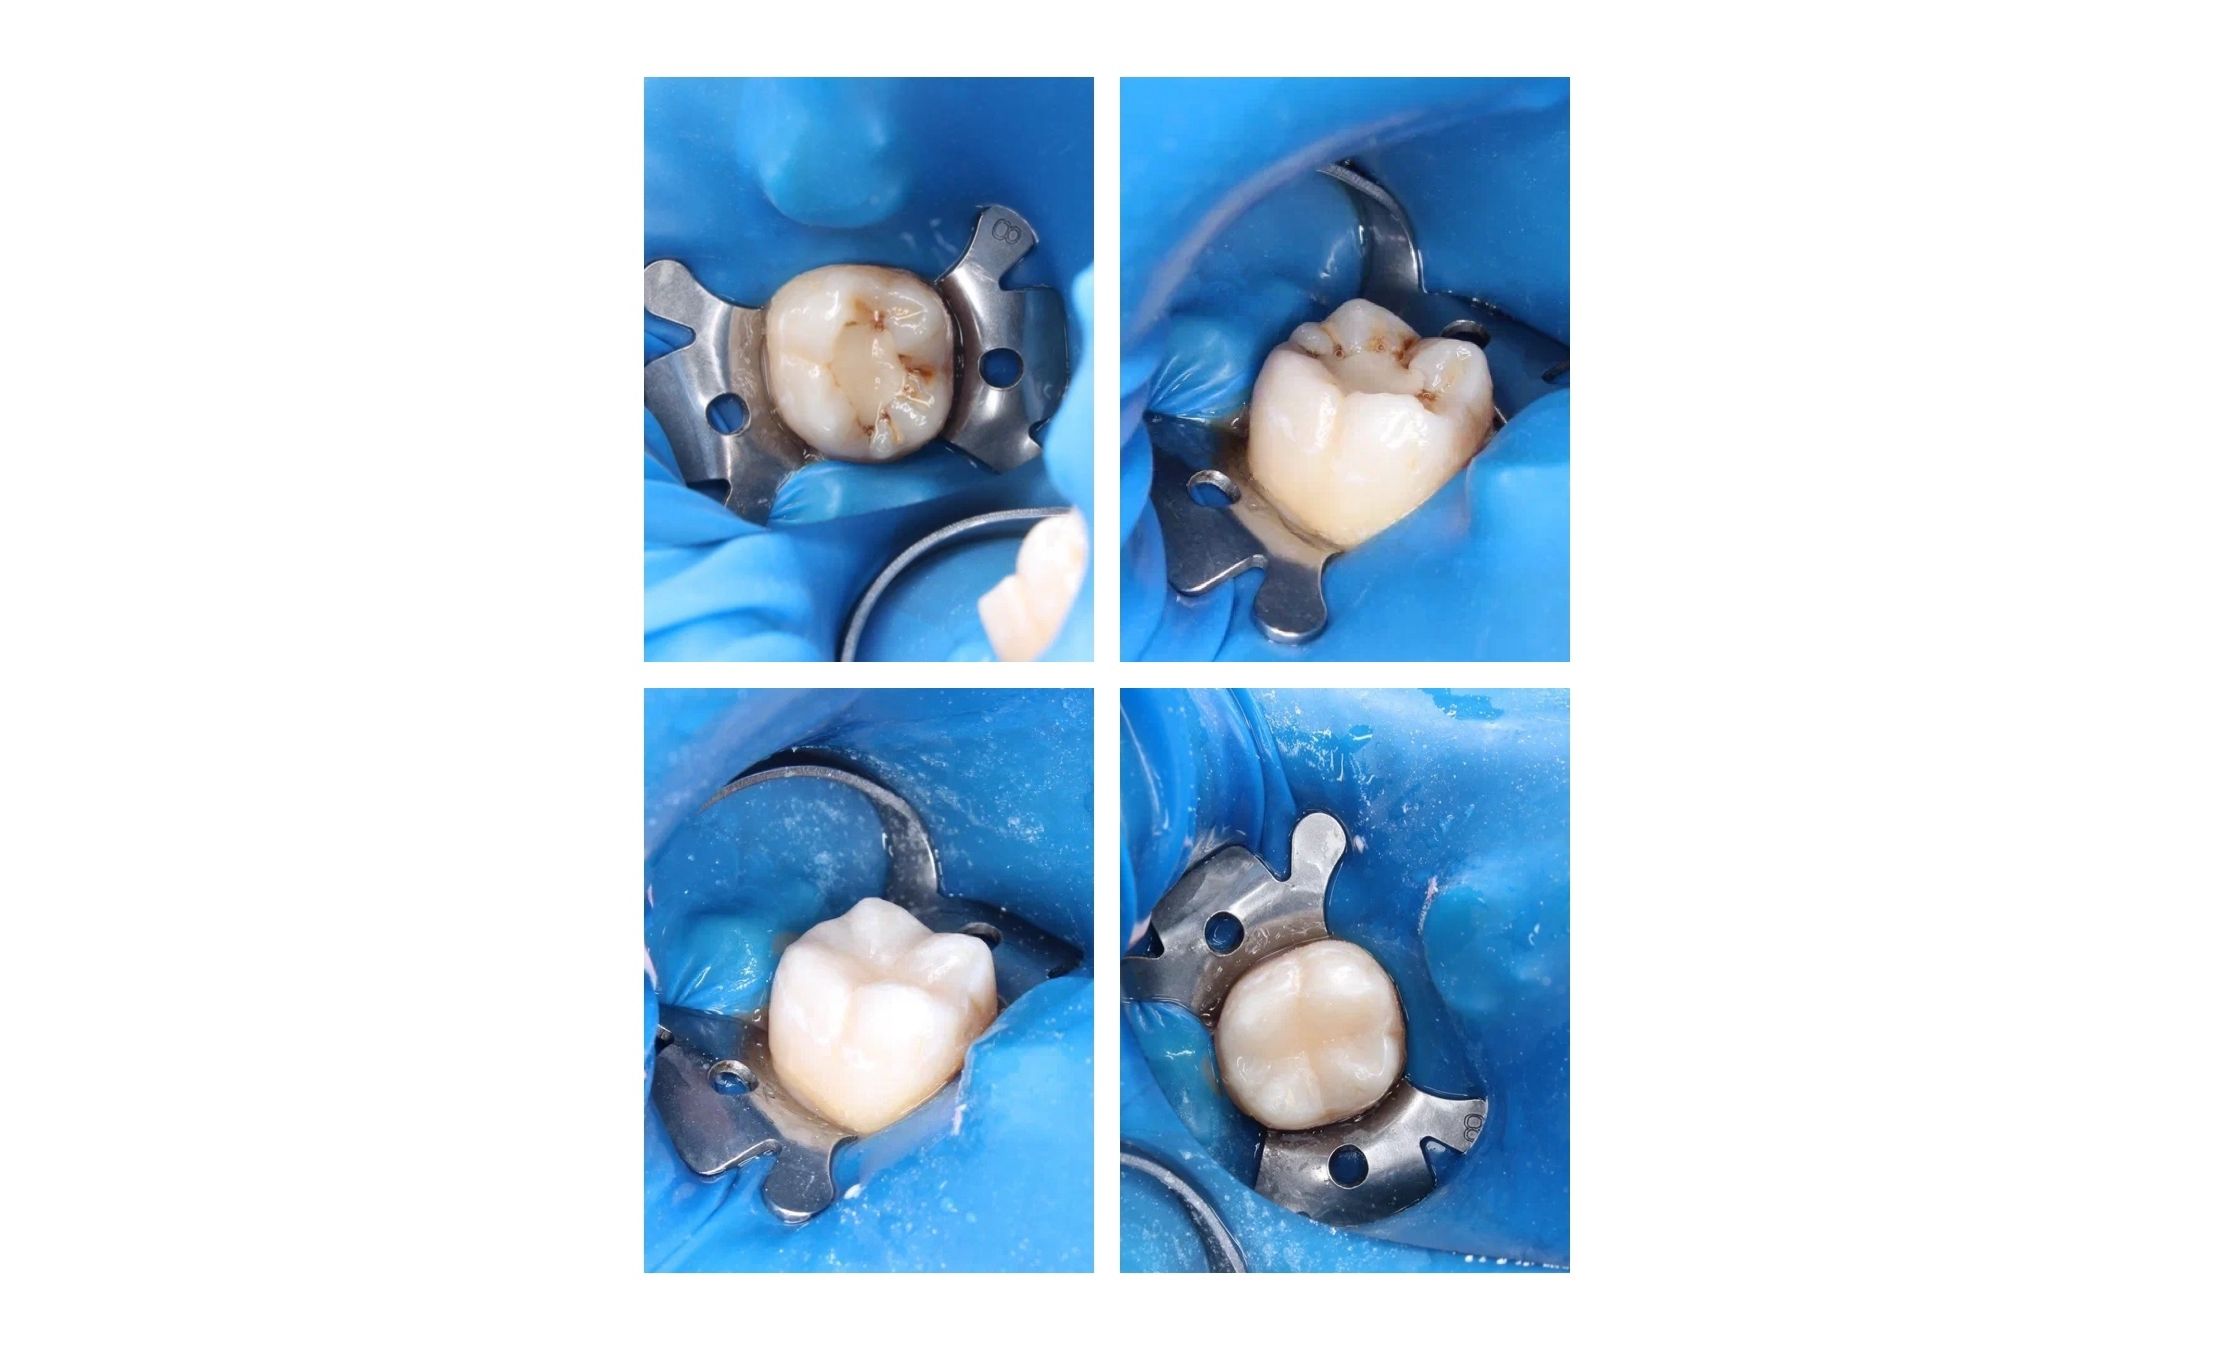

Замена функционально устаревшей пломбы.

Кейс врача-стоматолога Бояринова Сергея Эдуардовича.

Пациент обратился с жалобами на боли во время приема пищи. При осмотре была обнаружена устаревшая пломба. Была произведена замена функционально устаревшей пломбы.